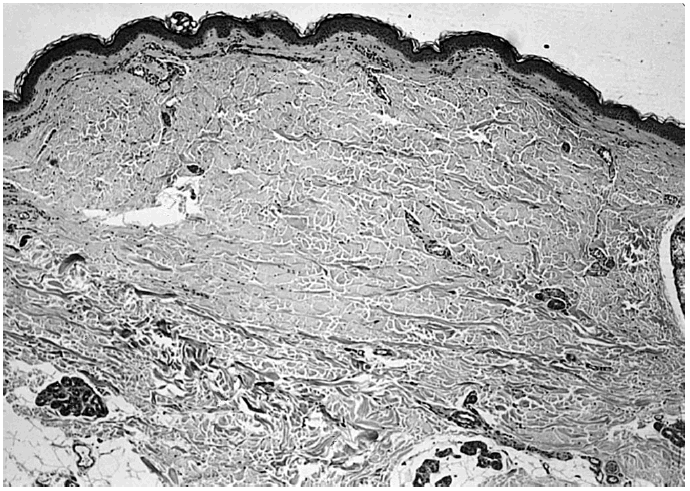

Se realizaron asimismo biopsias de la piel sana inmediatamente contigua a las lesiones. Las tinciones para fibras elásticas evidenciaron la desaparición de las mismas en la dermis papilar y su conservación en la dermis reticular (fig. 5).

Fig. 5.--Piel sana perilesional (paciente 1). Desaparición de las fibras elásticas elaunina y oxitalán en la dermis papilar (tinción fibras elásticas ×100).